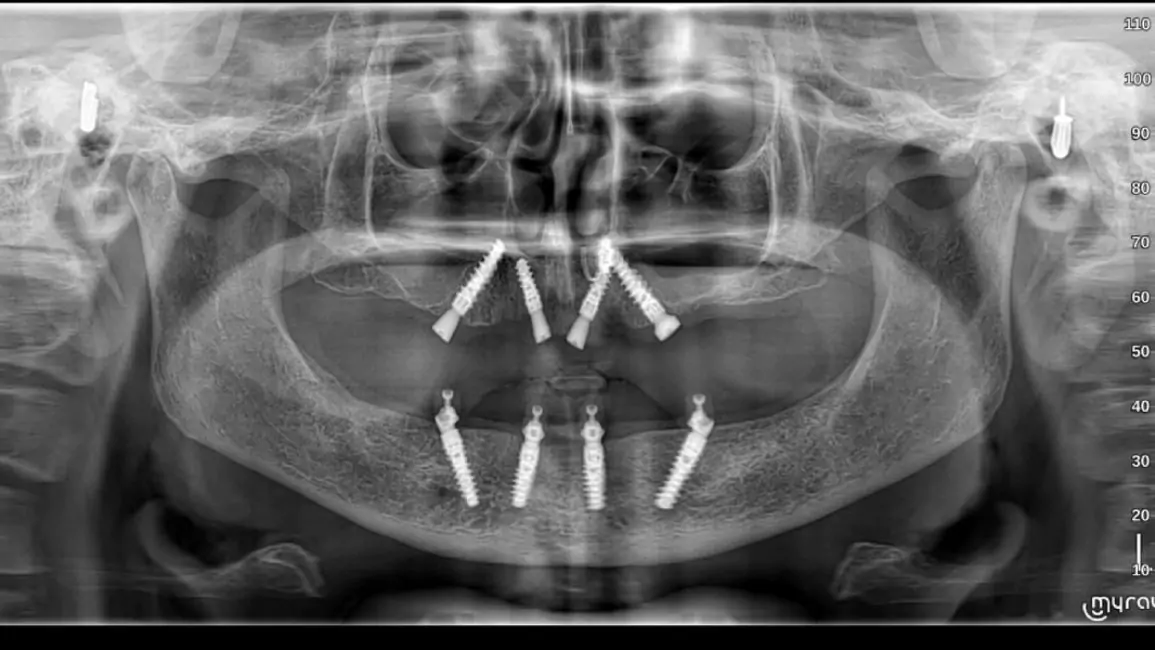

Since year 2000 we are Centre of excellence in implantology .We have done thousands of full mouth dental implant cases in last 25 years .We have a team approach where experienced implant surgeons , prosthodontists , maxillofacial surgeons , digital restorative dentists and lab technicians work together to deliver world class fixed teeth. We use multiple implant option from case to case. Some need All-on-4, some need All-on-6 or All-on-8 in selective cases.

All-on-4 Implants

It is a revolutionary concept in which only four implants support an entire arch of teeth. It is minimally invasive and cost-effective.

All-on-6 Implants

It is an advanced technique in which six implants support a full arch of teeth. It ensures superior stability, durability, and improved chewing function.